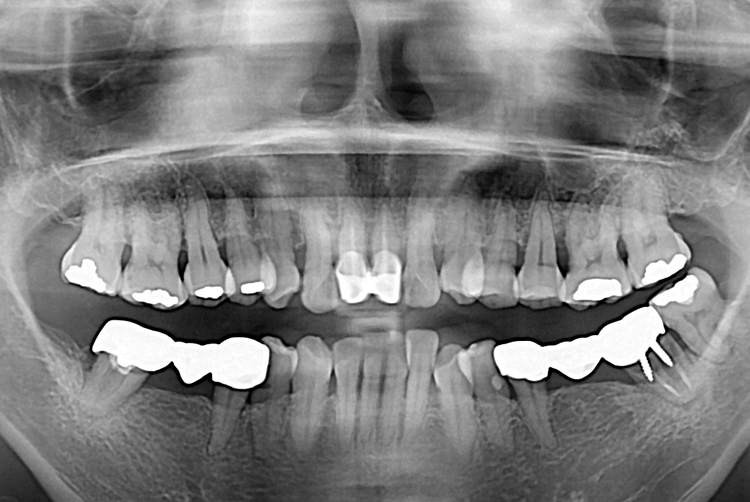

[임플란트] 임플란트

치료전 : 2017-07-13

치료후 : 2017-09-13

세종치과는 많은 환자와 다양한 케이스를 바탕으로 항상 편안한 임플란트 수술을 제공하고자 노력하고,

오래동안 튼튼히 쓸 수 있는 임플란트 수술을 가장 큰 목표로 삼고 있습니다